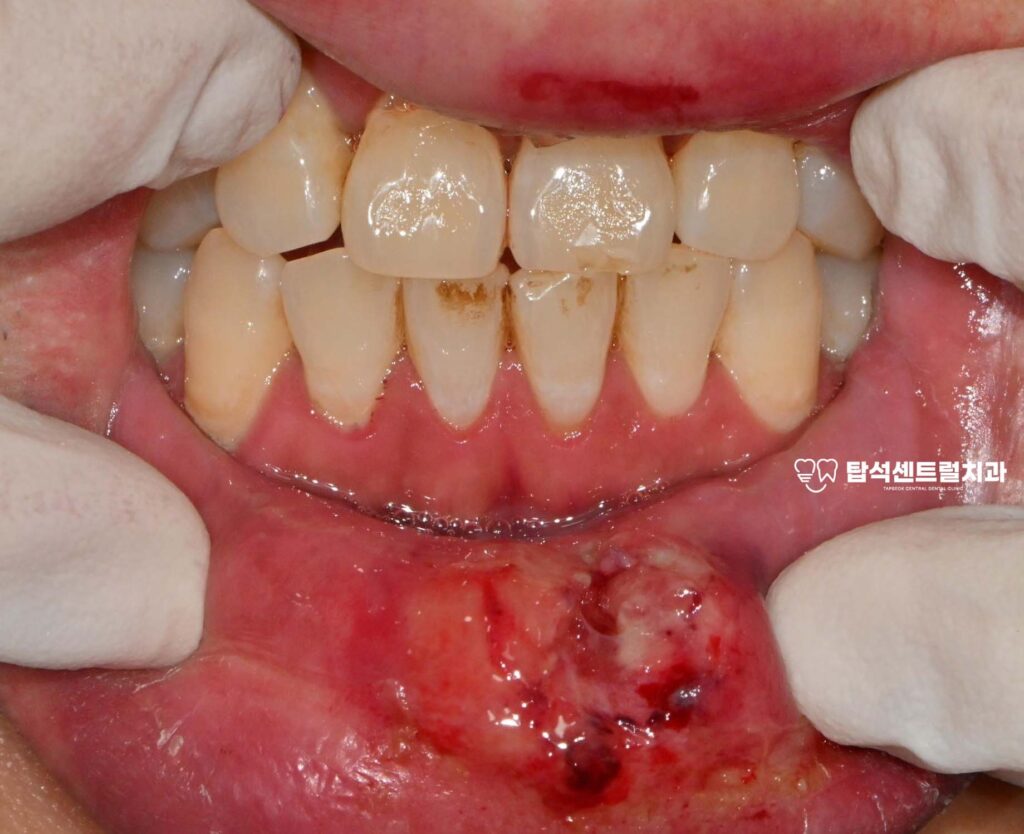

빙판길 낙상 사고가 발생하면

위아래 입술에 찢어진 상처가

생기는 경우가 많습니다.

또한 상악 중절치라고 불리는

윗쪽 앞부분에 금이 가거나

뿌리 부분까지 다칠 수 있습니다.

입술의 열상은 출혈이 동반되어

통증을 유발하기도 합니다.

하지만 연조직은 혈류 공급이

풍부하여 적절한 처치를 받으면

회복이 비교적 잘 되는 편입니다.